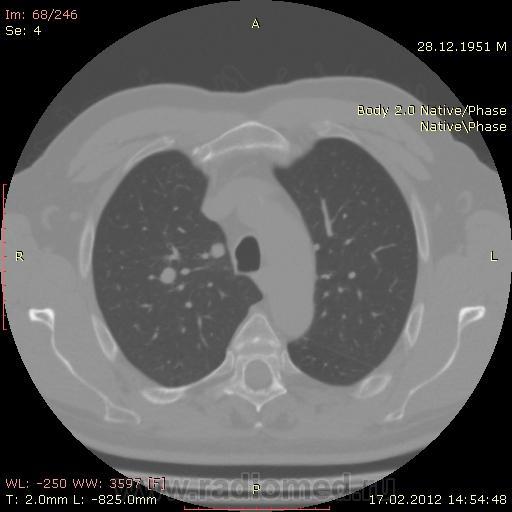

КТ.

В феврале 2012 года при очередном флюрографическом обследовании были обнаружены изменения в лёгких. По собственной инициативе было сделано КТ лёгких.

На первый взгляд - метастазы. А так, если родственник, искать выходы на МСКТ.

Согласен с Андреем Юрьевичем - наиболее вероятно - это метастазы...исключите первичное новообразование почки.